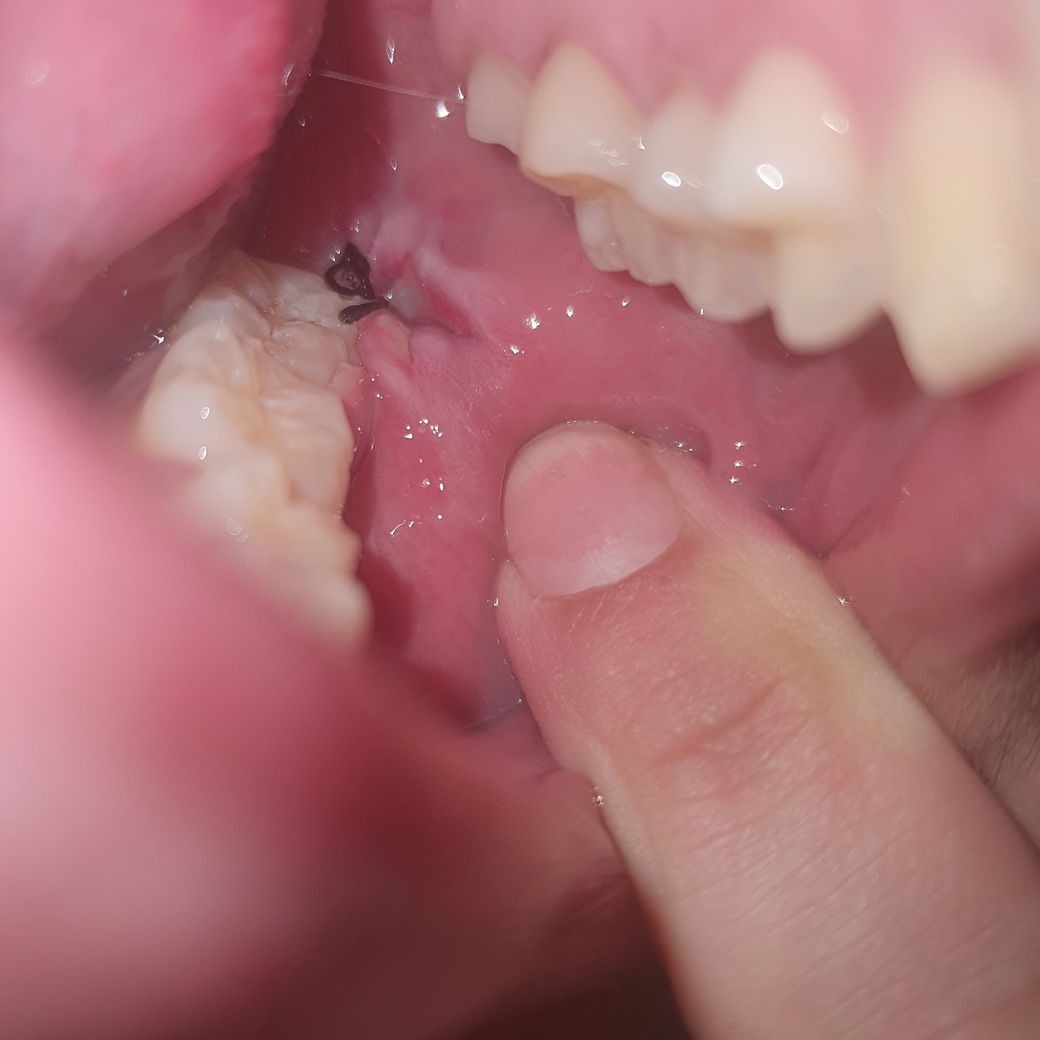

이게 어제..

이건 오늘 입니다.. 저거 흰색 이물질일까요? ㅠㅠ

계속 냅두면 볼살 차오를까요? 사진상으론 잘 안보이는데 많이 파였거든요..